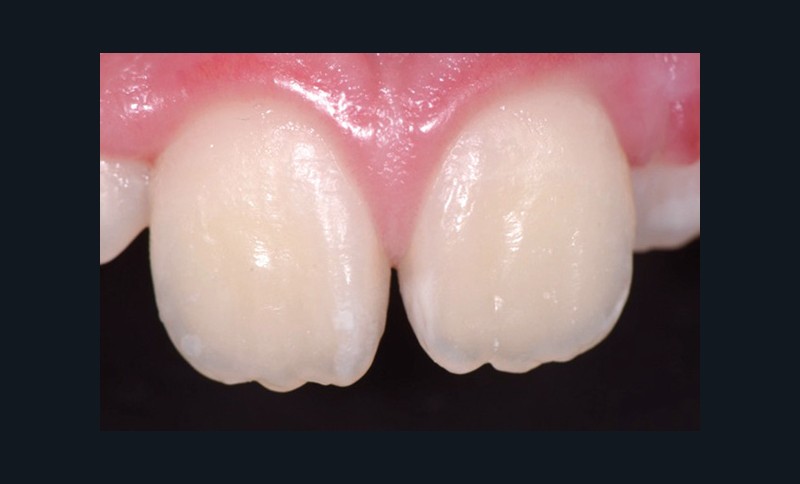

Traitement ultra-conservateur des taches de l’émail : bilan avec 5 ans de recul

Les auteurs de cette conférence nous proposent un algorithme pour résoudre le problème des taches blanches de l’émail. Ces techniques sont désormais utilisées avec succès depuis 10 ans. Tout d’abord il convient souvent de réaliser un éclaircissement préalable : celui-ci diminue le contraste entre la tache et le reste de la dent. Ensuite, avant de poser le champ opératoire, il faut choisir la teinte du composite qui sera nécessaire à la fin du traitement. Un sablage/fraisage des taches les plus profondes est alors réalisé, en fonction de la profondeur de la tache. Vient alors l’infiltration ou masquage optique, qui fonctionne sur les taches blanches : on passe une solution d’acide chlorhydrique, puis une solution d’hypochlorite de sodium, et si la tache est devenue blanche alors il est possible de passer à l’infiltration par la résine. Enfin, s’il subsiste une concavité visible, un composite viendra la combler. Le polissage clôt alors le protocole(fig. 11 et 12).